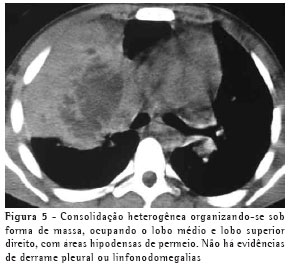

RESULTADOSO achado de imagem mais freqüente, presente nos 7 pacientes, foi consolidação de contornos mal definidos (Figuras 1, 2, 3 e 4), sendo que 5 deles tinham broncograma aéreo de permeio, principalmente na periferia da lesão. Em 3 casos, a consolidação organizava-se sob forma de massa. Em 6 dos 7 pacientes foram observadas, no interior das consolidações, áreas irregulares de escavação, múltiplas em 5 e única em 1 paciente. Em um dos casos não se observou escavação, mas ele mostrava áreas hipodensas de permeio, sugestivas de necrose (Figura 5). Apenas um dos pacientes apresentou nível líquido no interior das cavidades.